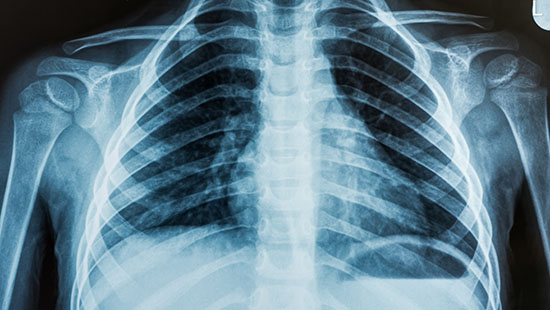

Chest x-ray of the lungs

• A chest X-ray takes a picture of your lungs, heart and rib cage to look for large masses or concentrations of fluid in the lungs;